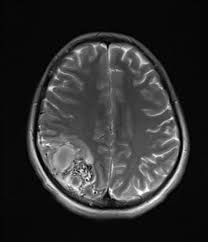

Cerebral Arteriovenous Malformation Radiology Case Radiopaedia Org Radiology Radiology Imaging Neurology